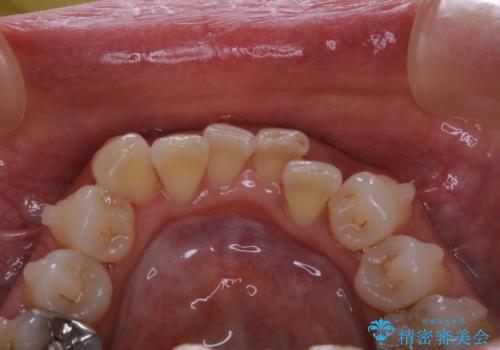

インビザラインの治療中の患者様のクリーニング前後写真です。

- インビザラインの矯正治療中に歯石や着色(ステイン)が付着してしまっていたため、歯科衛生士による専門的クリーニングを行いました。

今回はお口全体に歯石や着色(ステイン)が付着していたため、自費のPMTC(クリーニング)60分コースをご案内し、徹底的に除去しました。